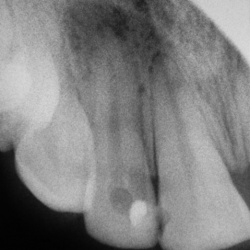

Какие мнения будут по снимкам?Первый пациент.Второй пациент.

Зубы.Первый пациент.Второй пациент.Третий пациент.